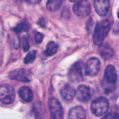

Based on digital whole slide scanning technique, artificial intelligence algorithms represented by deep learning have achieved remarkable results in the field of computational pathology. Compared with other medical images such as Computed Tomography (CT) or Magnetic Resonance Imaging (MRI), pathological images are more difficult to annotate, thus there is an extreme lack of data sets that can be used for supervised learning. In this study, a self-supervised learning (SSL) model, Global Contrast Masked Autoencoders (GCMAE), is proposed, which has the ability to represent both global and local domain-specific features of whole slide image (WSI), as well as excellent cross-data transfer ability. The Camelyon16 and NCTCRC datasets are used to evaluate the performance of our model. When dealing with transfer learning tasks with different data sets, the experimental results show that GCMAE has better linear classification accuracy than MAE, which can reach 81.10% and 89.22% respectively. Our method outperforms the previous state-of-the-art algorithm and even surpass supervised learning (improved by 3.86% on NCTCRC data sets). The source code of this paper is publicly available at https://github.com/StarUniversus/gcmae

翻译:根据数字整体幻灯片扫描技术,深层学习所代表的人工智能算法在计算病理学领域取得了显著成果。与其他医学图像相比,如光学成像(CT)或磁共振成像(MRI),病理图象更难说明,因此极缺乏可用于监督学习的数据集。在这项研究中,提出了一种自我监督的学习模型(SSL),即全球反光遮罩自动算法(GCMAE),它能够代表整个幻灯片图像的全球和地方域特性,以及极好的交叉数据传输能力。Camelyon16和NCETCRC数据集用来评估我们模型的性能。在处理不同数据集的传输学习任务时,实验结果表明,GCMAE的线性分类准确性优于MAE,该模型可分别达到81.10%和89.22%。我们的方法超越了先前的状态-艺术算法,甚至超越了监督性学习能力(在NCCRC/SAR代码源的3.86 %上,可公开查阅的MARC/SALmas。